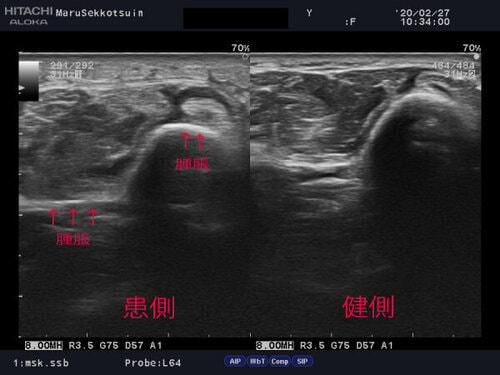

いつものように問診、視診、触診、そして確認の為、エコー検査。

intersection2.jpg

写真の通り、腫れが著名であり、手首を動かすと"ギシギシ"と、

鳴るところが、今回のポイントでございます。